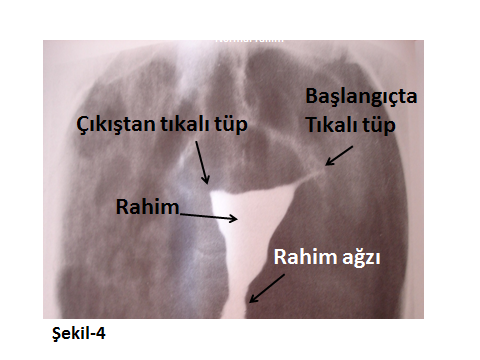

Aşağıda farklı HSG görüntüleri ile konu görsel hale getirilmeye çalışılmıştır.

Tıpta yeni bir çağ açan ilk tüp bebek Louise Brown 25 Temmuz 1978’de İngiltere’de doğdu. 9 yıl çocuk özleminde olan bu ailede sorun anne Lesley Brown’un geçirdiği 2 dış gebelik operasyonu sonucunda her iki tüpünü de kaybetmesi idi. Bu örneğe benzer olgular ile cerrahiye ya da geçirilmiş enfeksiyonlara bağlı tüp fonksiyonunu kaybetmiş ailelerde tetkik sırasındaki HSG’de Şekil-4’teki görüntüler saptanacaktır. Günümüz teknolojisinde eskiden çocuk sahibi olmaları imkansız olarak görülen bu kişiler için günümüzde Tüp bebek (IVF) yöntemi gerçek bir ümit olabilmektedir.

Şekil-4’te her iki tüp tıkanıklığının HSG yöntemi ile ne kadar büyük olasılık içinde saptanabildiği görülmektedir.